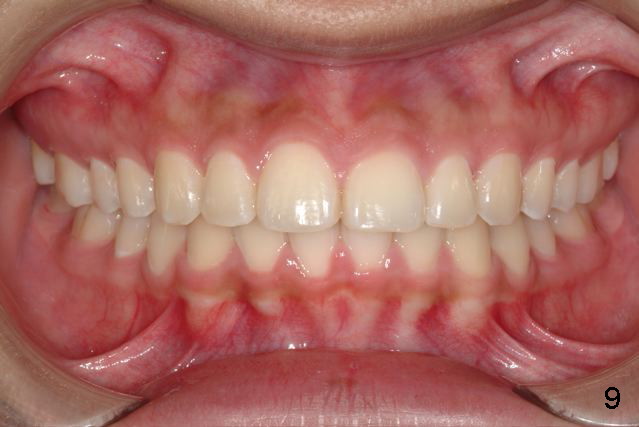

Answer: I was afraid tooth #8 would try to rotate (Fig.).  I do not like U bonded retainers as much as lower but I thought maybe in this case due to #8 initial position.  I have provided 2 removable retainers to fit over for insurance!

Excellent thinking.  According to the final photos, you must have done something to overcorrect the rotation of the two centrals.  Did you do it with purpose or by accident?  How did you do it, although Amy may not like it.  It seems to me that there is no practical way to overcorrect rotation.